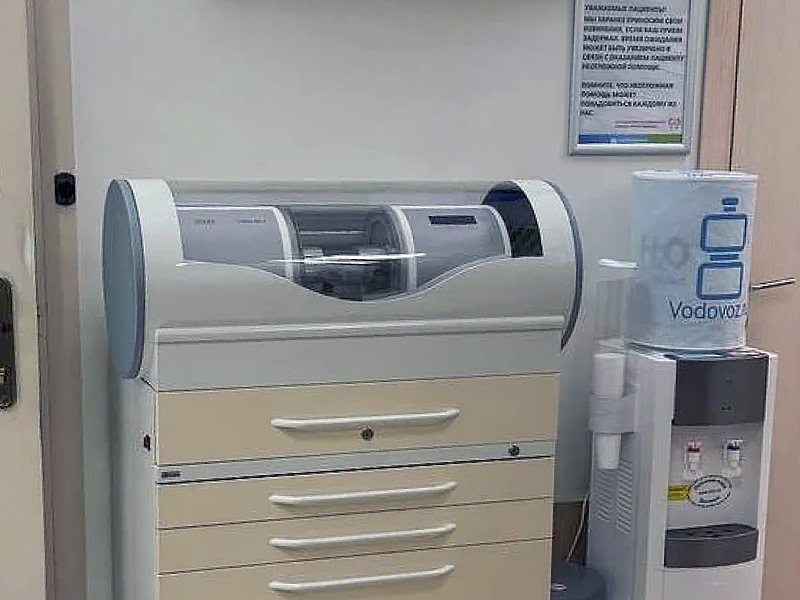

Наше оборудование

- Быстрота проведения ортопедических мероприятий: в нашем Центре есть собственная зуботехническая лаборатория